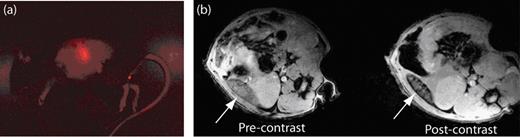

Fluorescent and magnetic resonance (MR) images revealing the biodistribution of B cells in mice. (a) Fluorescent image of a mouse that has been injected with B cells that have been labeled with ultrasmall superparamagnetic iron oxide (USPIO) and the fluorescent dye CellVue® NIR815. The fluorescent image clearly shows the localization of B cells within the spleen. (b) MR images of the spleen (white arrow) before and after the injection of the USPIO-loaded B cells. The migration of USPIO-loaded B cells to the spleen results in a loss in signal intensity on T2-weighted images.